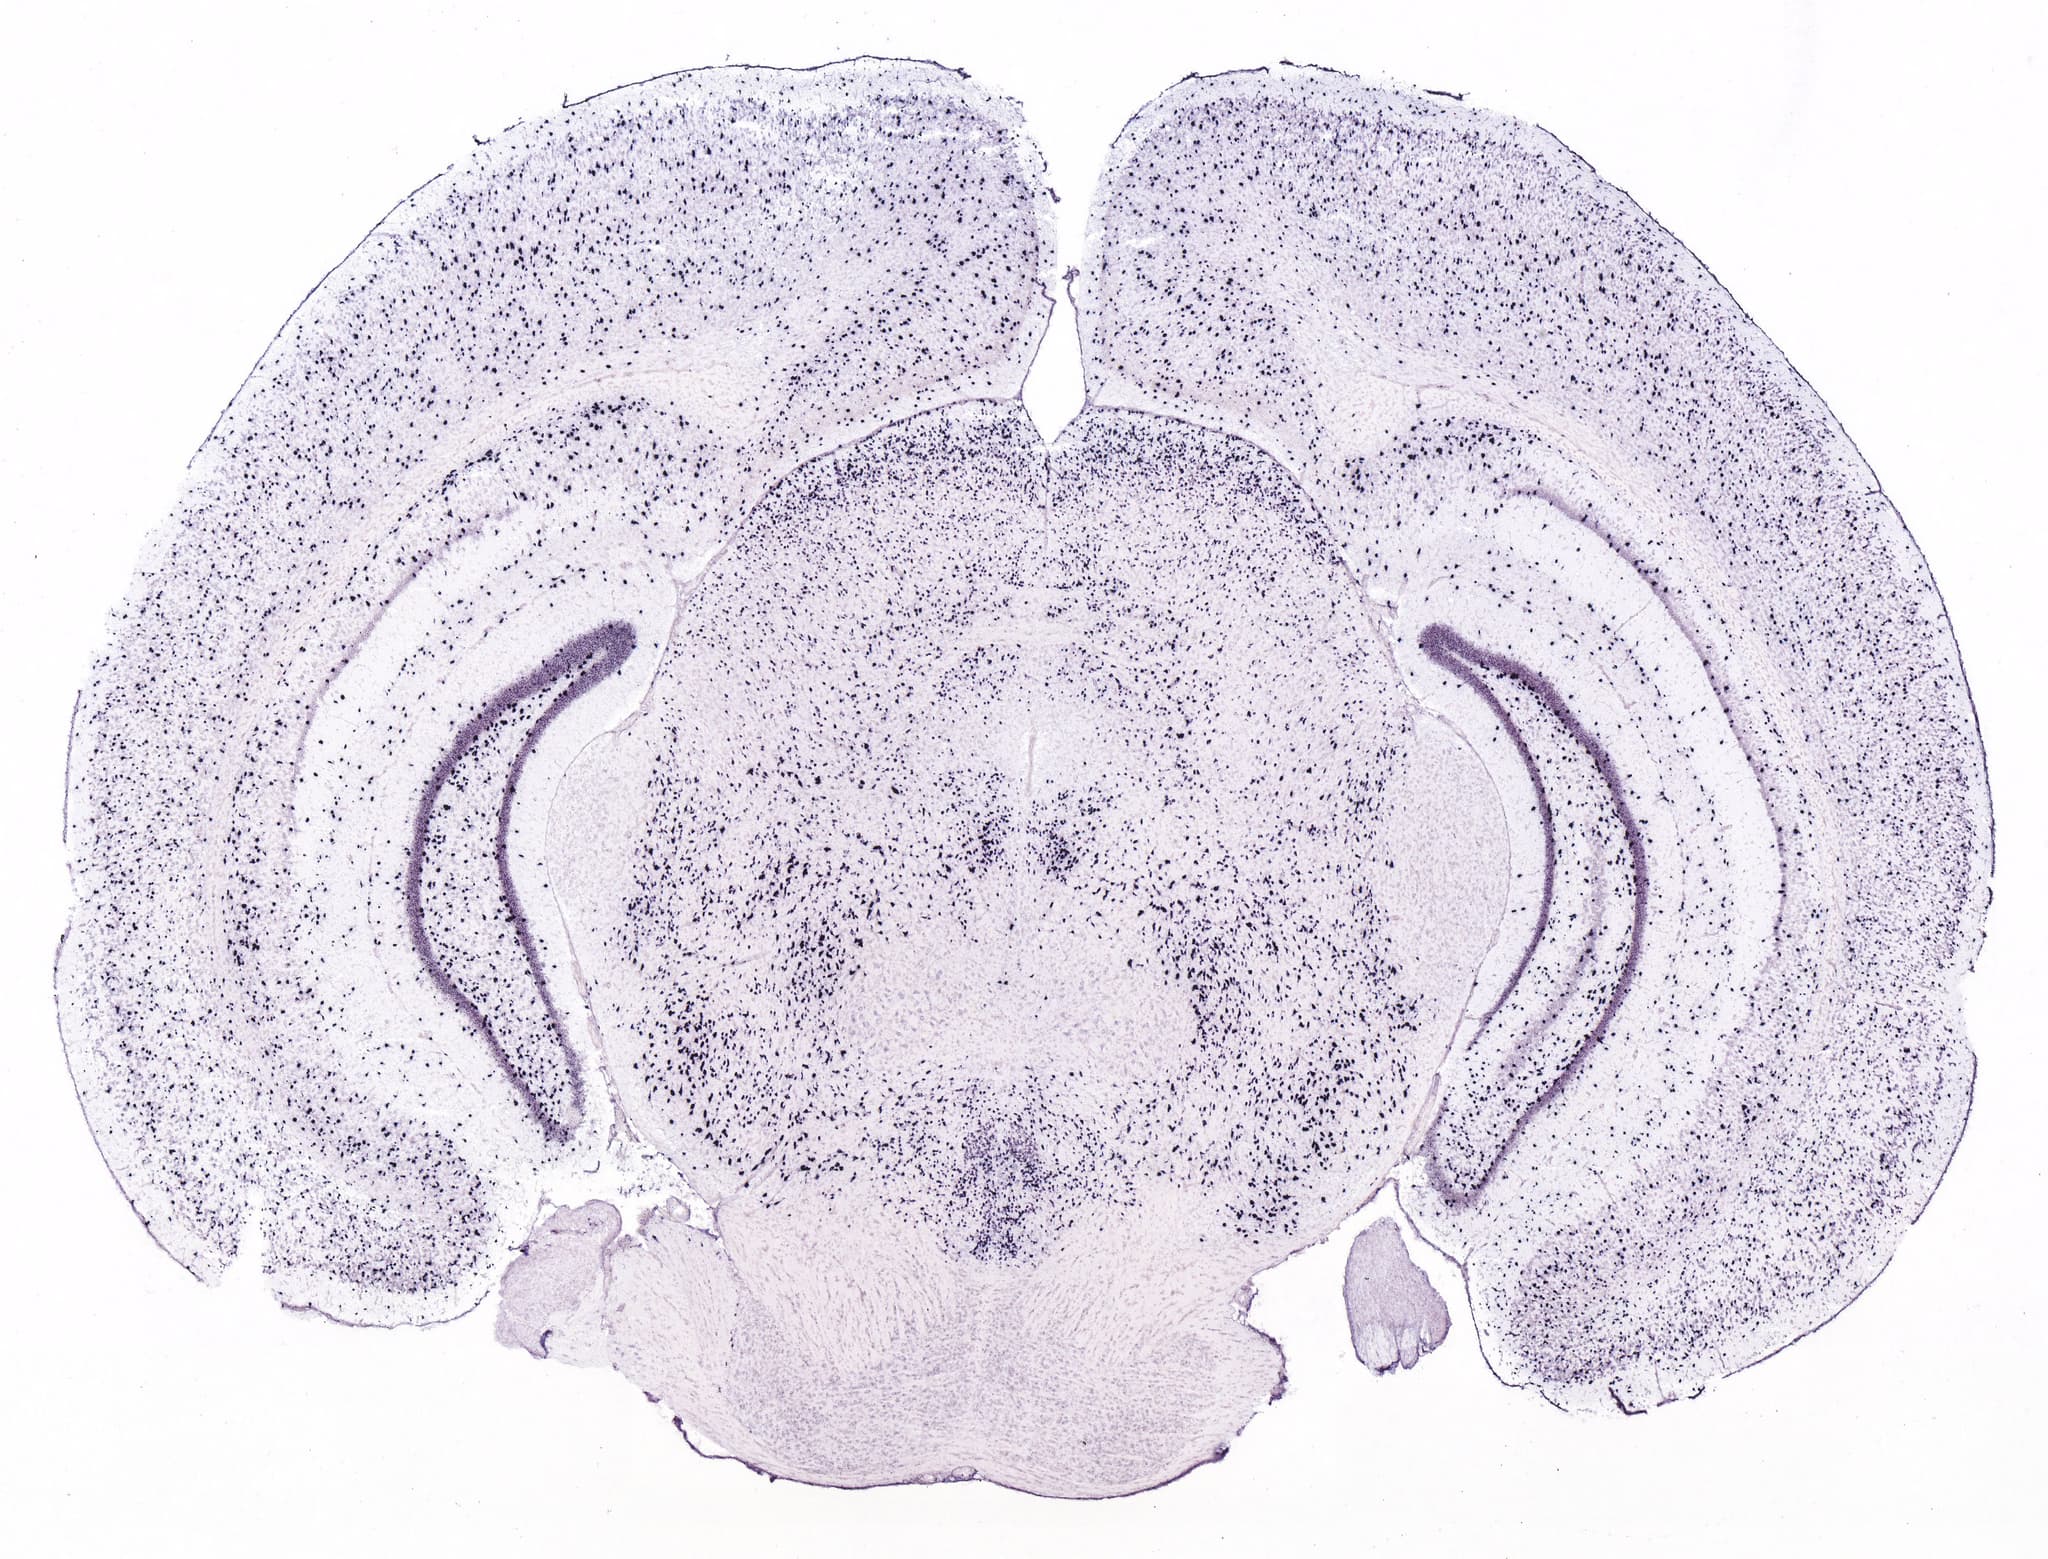

A robust software for performing K-Means clustering and data visualization on mouse brain grid annotations.

I created this software during my research project as a Motorola Solutions Foundation Scholar, offering an easy and robust solution to performing machine-learning models on gene expression data. This software has made it incredibly easy to run K-Means clustering on grid expression values across data sourced from the Allen Mouse Brain Atlas.